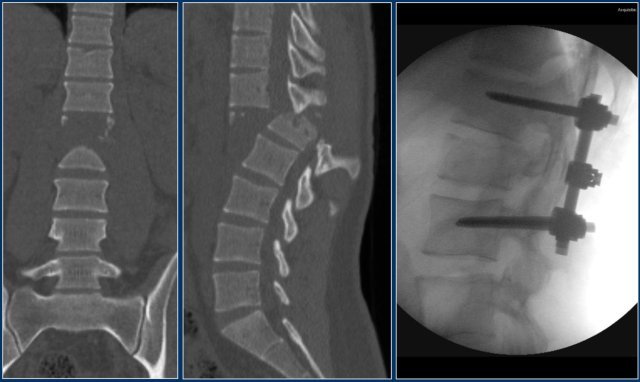

The findings are:

1. Morphology: Distraction - 4 points

2. PLC: always torn in posterior distraction - 3 points

3. TLICS based on imaging: 7 points

The key point in this case is that you should not describe this morphology as burst - 2 points.

The horizontal fractures on the posterior side and the increased interspinous distance indicate distraction, which means a higher score for morphology.

Always go for the highest possible score in TLICS.